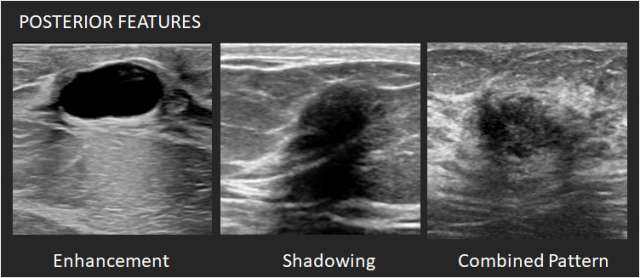

Posterior features: Posterior features represent the attenuation characteristics of a mass in respect to its acoustic transmission.

- Enhancement – There is a column that is more echogenic deep to the mass. One criterion for cyst diagnosis is enhancement.

- Shadowing – There is attenuation of acoustic transmission with the area posterior to the mass appearing darker. Shadowing is associated with fibrosis, with or without an underlying carcinoma. Macrocalcifications can also cause shadowing.

- Combined pattern – There is more than one pattern of posterior attenuation.